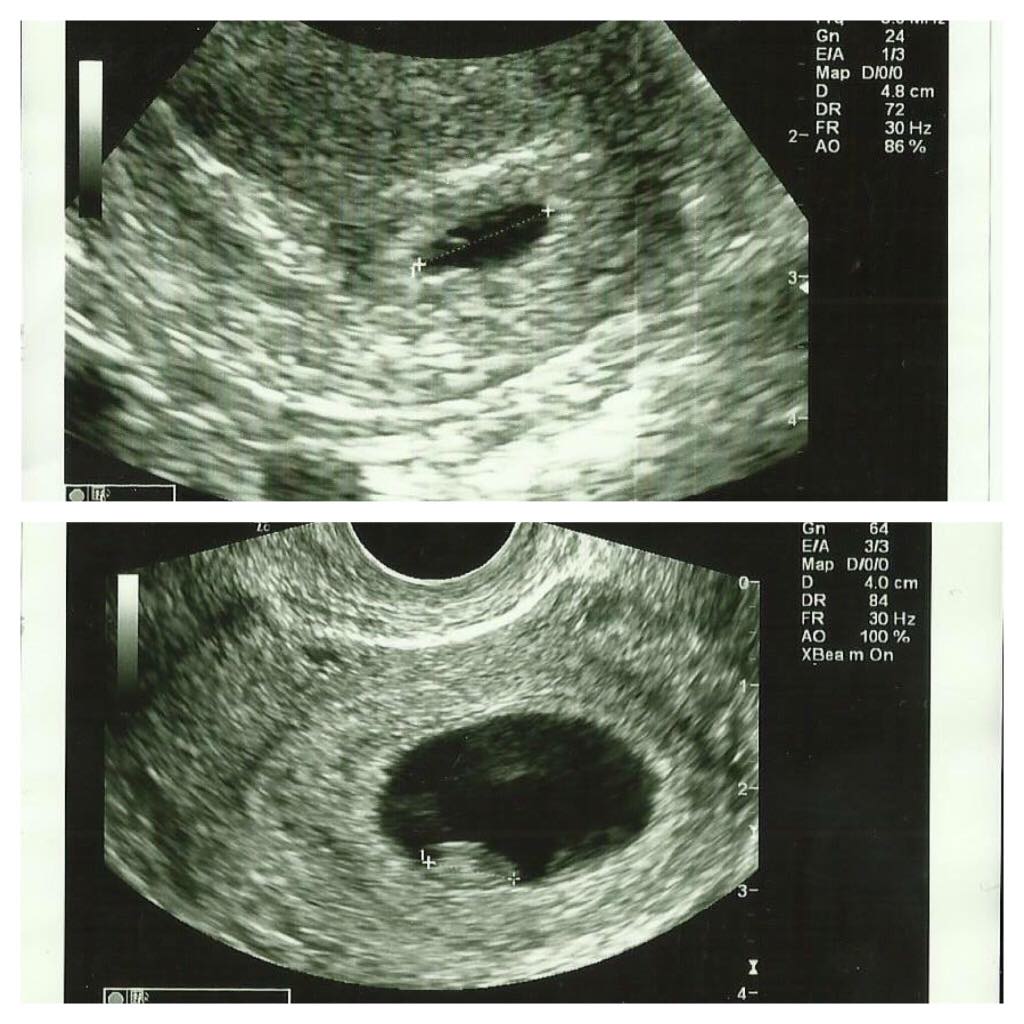

Ylempi kuva vanhempi ja alempi tänänen :) meidän pieni piti vastata kokoa 6+3 mutta olikin vähän tsempannu ja kasvanu jo rv 6+6 <3

Ja se tunne kun sydänlyö siinä näytöllä oli jotain hienointa mitä olen koskaan nähnyt <3 voi kumpa te kaikki saisitte sen viellä kokea! Pää lyö ihan tyhjää :D niin onnellinen fiilis ja helpottunut että siellä on pieni ihme kyydissä eikä mikää tuulimuna!

Kaikki oli just niinkuin piti :) ja LA aikaistu yhellä päivällä eli 26.10 :)